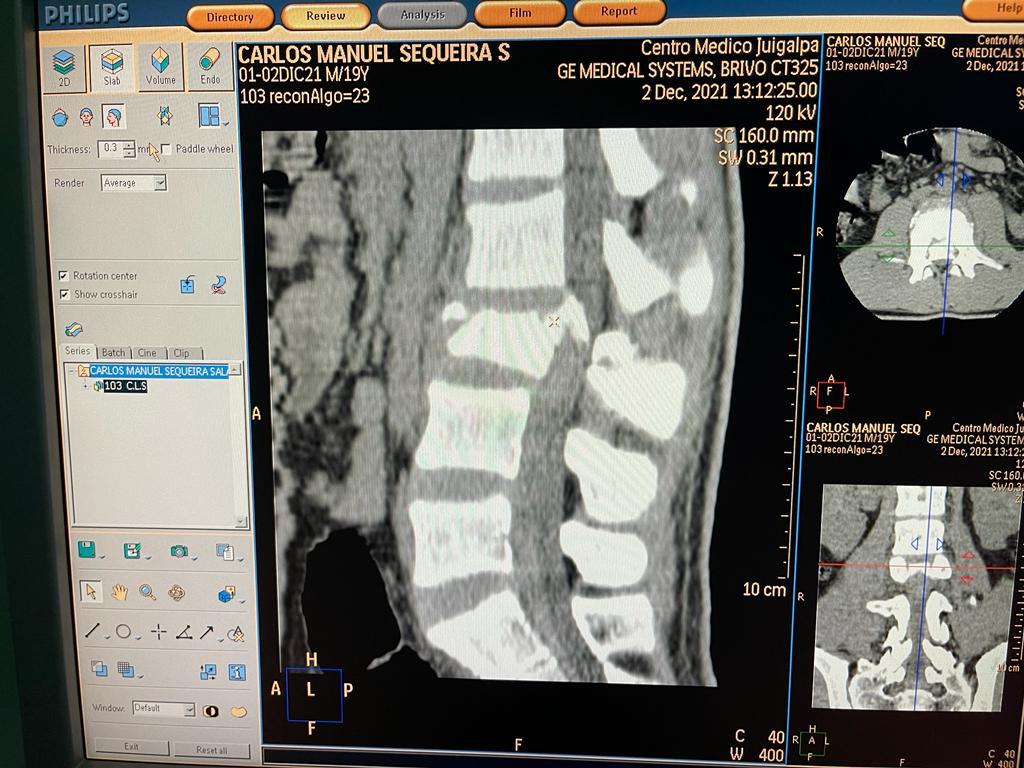

2. Discectomía Lumbar

Cirugía mínimamente invasiva para eliminar una hernia discal lumbar que causa dolor irradiado (ciática), debilidad o adormecimiento.

Indicaciones

- Dolor lumbar irradiado a la pierna

- Hernia discal lumbar con compresión radicular

- Síntomas neurológicos persistentes